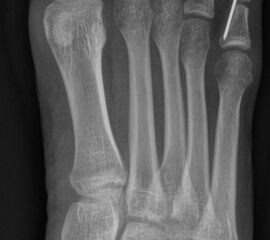

Schneiderballen: MT V Osteotomie

Diese Osteotomie ist indiziert bei stark lateralisierten MT V Köpfchen wie es nicht selten in Kombination mit einem Hallux valgus, einem Ballen-Hohlfuß oder Klumpfuß vorkommt (Abb. 25).

Dementsprechend führen wir die MT V Osteotomie häufig als Kombinationseingriff durch. Sie kann subcapital im Sinne der Kramer-Osteotomie oder adduzierend am Schaft durchgeführt werden (Abb. 26).

Abb. 26 a-e: adduzierende Osteotomie. (a) Fuß präoperativ d.p. und (b) als Schrägaufnahme. Im Schrägbild gut sichtbar die subluxierte 5. Zehe. (c) intraoperative Aufnahme der MT V Schaftosteotomie. (d) Fuß postoperativ d.p. und (e) als Schrägaufnahme.